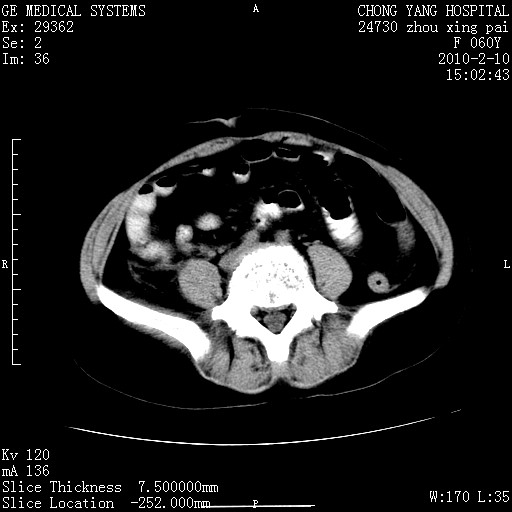

标题: CT24682:F60Y 腹痛 其它不详 [打印本页]

标题: CT24682:F60Y 腹痛 其它不详

1)胆总管末端梗阻,不排除结石所致可能。2)胰腺炎。3)慢性胆囊炎可能。4)左侧输尿管上段扩张。5)少量腹水。6)双侧少量胸腔积液,伴两下肺部分肺萎陷。

1)胆囊炎。2)胆源性胰腺炎。3)右肾周筋膜增厚,肾旁前间隙积液。4)左侧输尿管上段扩张。5)少量腹水。6)双侧少量胸腔积液,伴两下肺部分肺膨胀不全。

1)胆总管末端梗阻。2)胰腺炎。3)慢性胆囊炎可能。4)左侧输尿管上段扩张。5)少量腹水。6)双侧少量胸腔积液,伴两下肺部分肺萎陷。